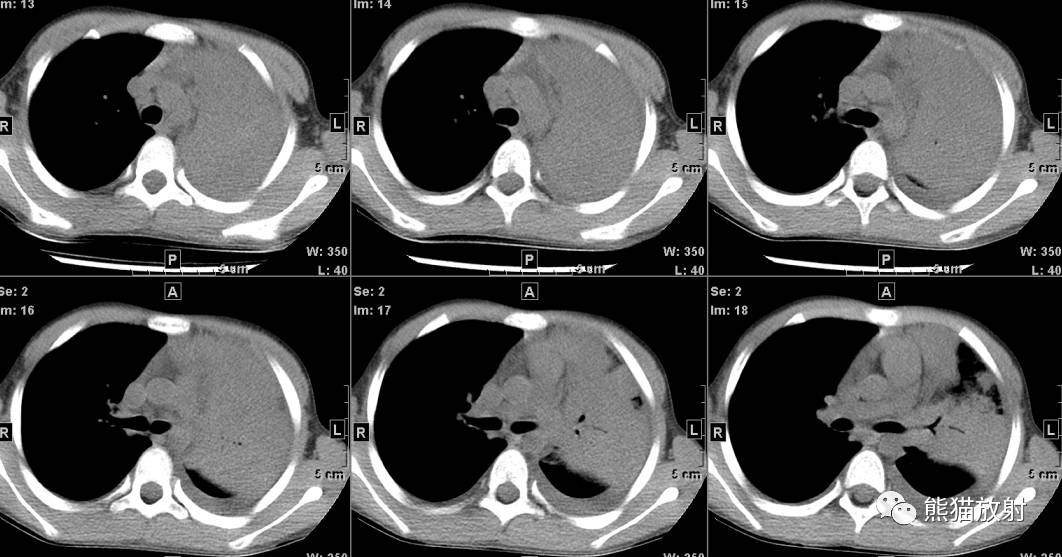

↓ 右肺中央型肺癌(鳞癌)并右下肺不张(X、CT)